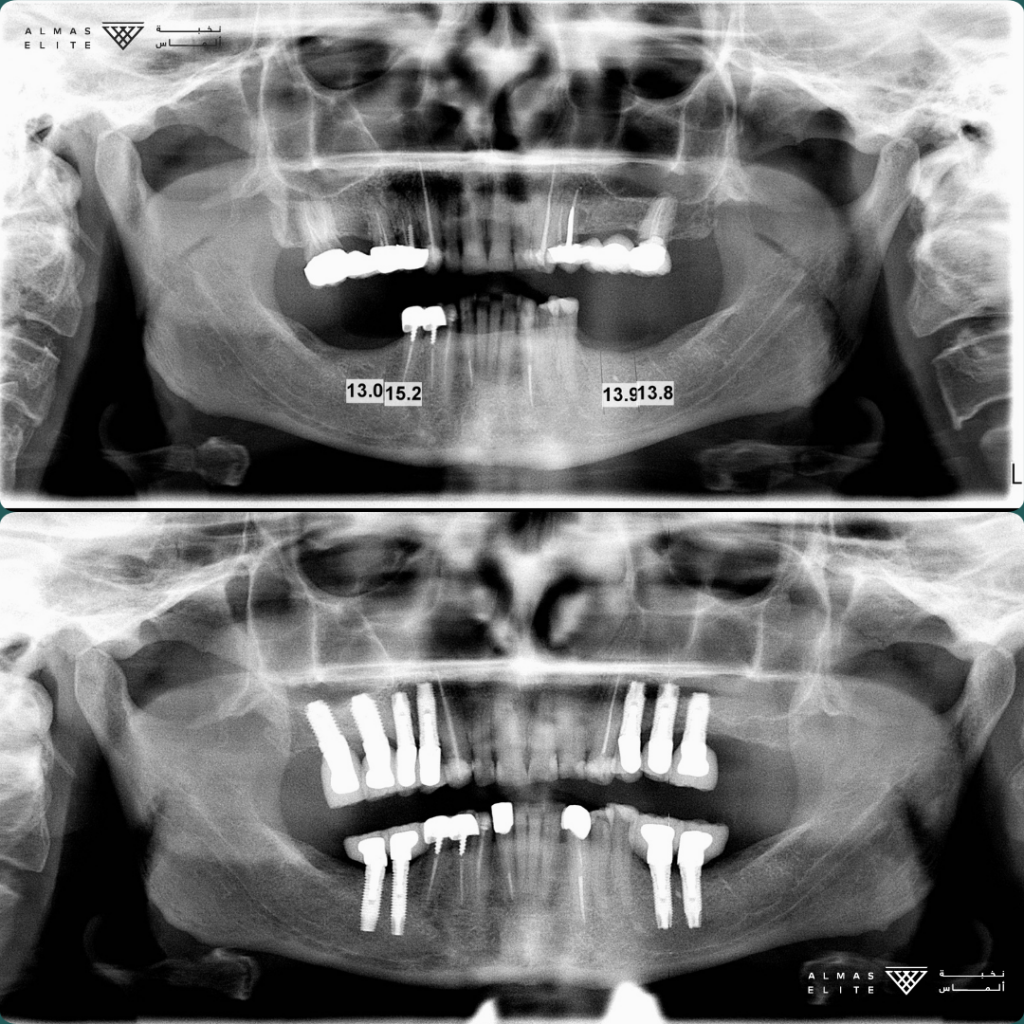

القرار النهائي لملاءمة الزراعة يتم بعد استشارة الطبيب، والفحص السريري، والتصوير الإشعاعي (مثل الأشعة ثلاثية الأبعاد) حسب الحاجة.

• الفحص الكامل: يشمل الأشعة ثلاثية الأبعاد وتحليل جودة وكثافة العظم.

٣) المرحلة الجراحية (Stage 1)

• الزراعة التقليدية: بعد شفاء موضع الخلع بـ 6–8 أسابيع في كثير من الحالات.

• الزراعة الفورية: تتم بعد الخلع مباشرة بشرط توفر المعايير اللازمة.

تليها فترة اندماج عظمي تستغرق من 3 إلى 6 أشهر حسب الحالة الصحية وجودة العظم.

٤) المرحلة التركيبية (Stage 2)

• فتح اللثة وتركيب Healing Abutment فوق الزرعة.

• أخذ المقاسات أو إجراء المسح الرقمي للأسنان.

• تركيب التاج النهائي في العادة خلال أسبوعين تقريبًا من أخذ المقاسات.